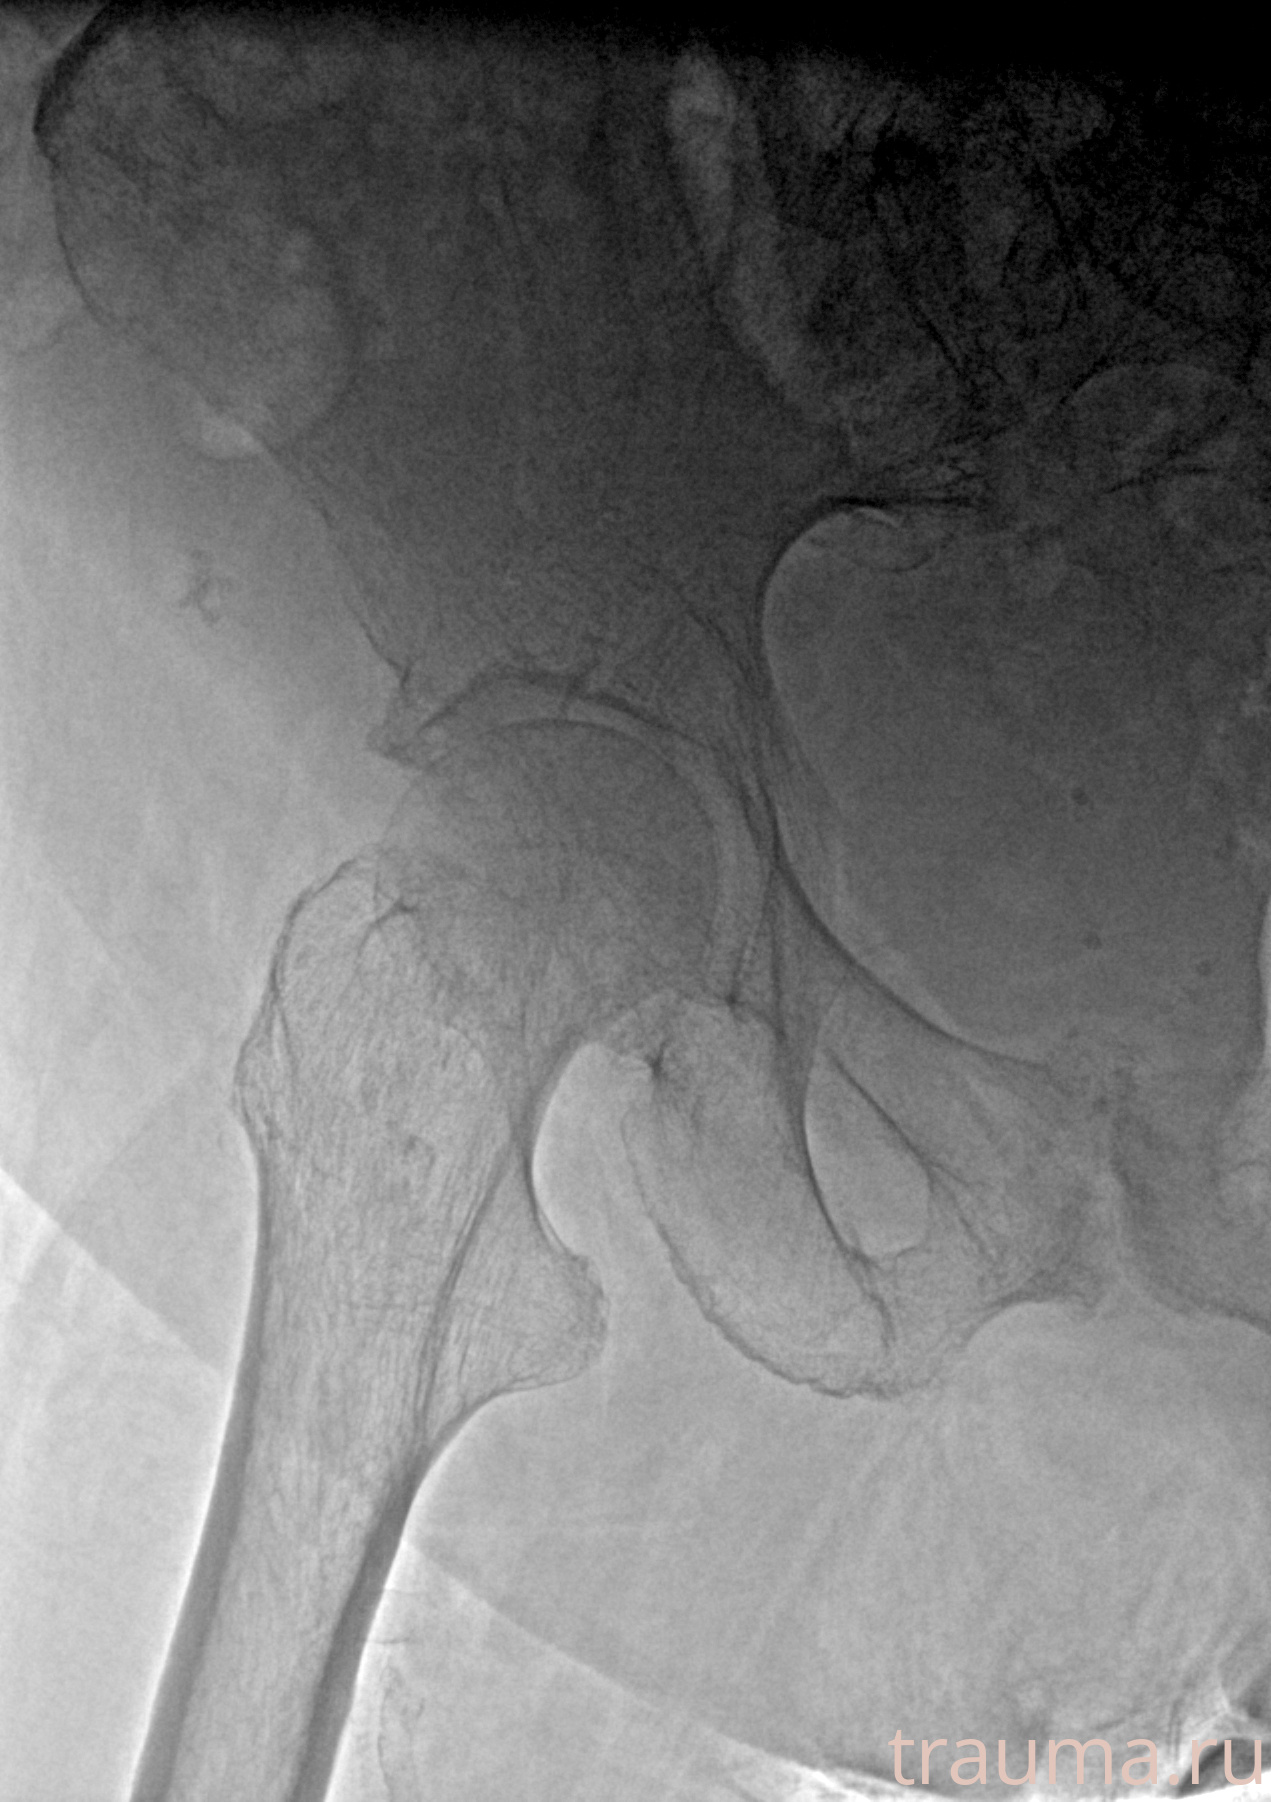

Рентгенограммы

Рентген на дому: по вашему адресу приезжает врач-рентгенолог, травматолог-ортопед с мобильным рентгеновским аппаратом, проводит диагностику травмы или заболевания, делает необходимые рентгенограммы, дает рекомендации по дальнейшему лечению. Получить качественные снимки в домашних условиях возможно благодаря уникальной методике, разработанной МосРентген Центром для института  Склифосовского